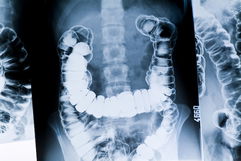

6. Trombosis intestinal

La trombosis intestinal surge en las venas del intestino, provocando la interrupción del flujo sanguíneo hacia el intestino grueso o delgado, y la muerte del tejido intestinal, conocido como infarto intestinal, lo que resulta en dolor abdominal intenso, náuseas y vómitos.